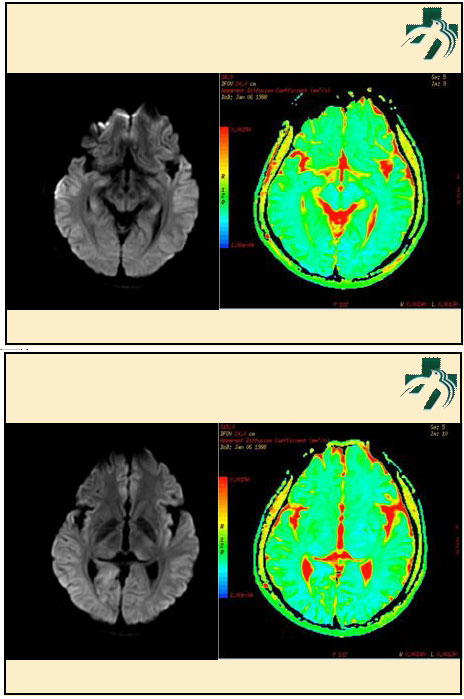

奴卡氏菌感染

第九期三博

读片会

病例之四

北京协和医院 提供

男性,22岁。自觉虫咬后皮疹、肢体麻木4月